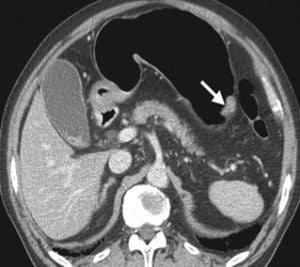

She underwent a CT scan (Figure 2) abdomen with IV contrast and Positive emission tomography (PET) scan, which confirmed the absence of metastasis. The biopsy results confirmed grade III gastric adenocarcinoma with gastric dysplasia, anaplasia, increased nucleus to cytoplasm ratio, and other features of cancer, associated with H. pylori infection (Figure 3). She promptly started on antibiotics for H. pylori and underwent partial gastrectomy, including adjacent lymph nodes. Post-surgery, her management was continued by the Oncology department.

Figure 3: Abdominal CT scan showing gastric cancer